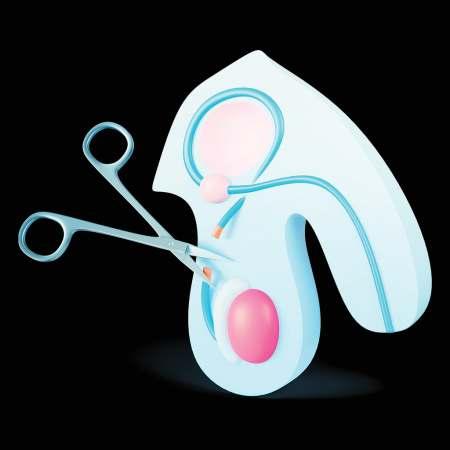

ESTERILIZACIÓN MASCULINA Y FEMENINA

La esterilización quirúrgica masculina o femenina tiene como desventaja principal que es irreversible, de manera si la persona se arrepiente no hay solución a su caso, en general no tiene casos secundarios, salvo los propios de un pro-

ligadura de trompas, que consiste en cortar, atar o bloquear las trompas de Falopio para evitar que los óvulos lleguen al útero, en hombres, se realiza la vasectomía, que implica cortar y sellar los conductos diferentes para evitar la

cedimiento quirúrgico como dolor después de la operación, la esterilización es un método anticonceptivo permanente que busca impedir la fertilidad de manera irreversible, en mujeres, esto se logra a través de la

liberación de esperma durante la eyaculación, ambos procedimientos son altamente efectivos, con una tasa de éxito superior al 99%, y no afectan el deseo sexual ni la capacidad de disfrutar de relaciones sexuales.